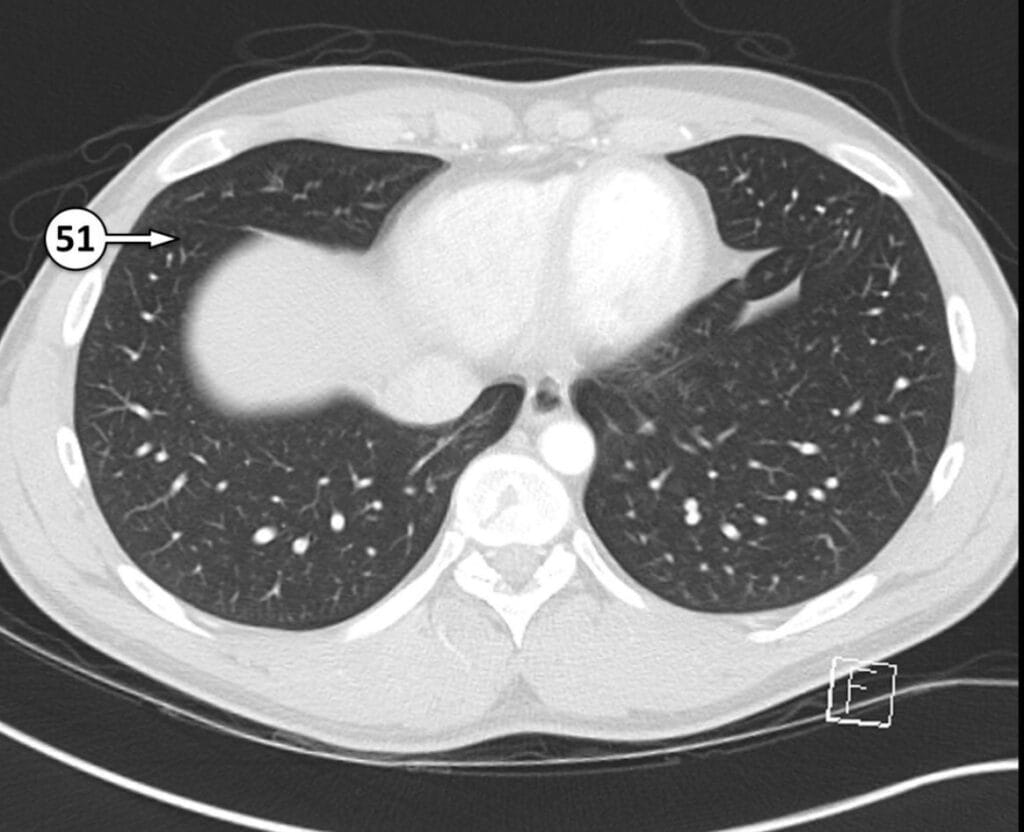

51. anterior basal segment of RLL